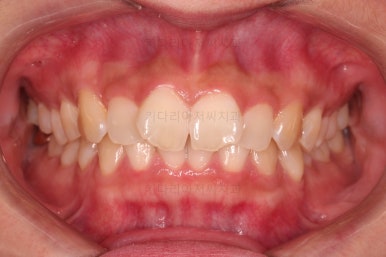

초진 시 입안의 모습입니다.

어금니 쪽은 약간 삐뚤긴 하지만 꼭 교정해야 할 정도는 아니고, 불편감 없이 비교적 잘 맞물리는 상태였습니다.

다만, 앞니ㅉㄱ이 공간이 부족해서 중간 치아들이 많이 회전되어있는데, 이를 환자분들의 표현에 따르면 "나비치아" 라고 부릅니다.

위아래 중간 앞니가 모두 나비치아처럼 되어있고요.

윗니가 아랫니보다 앞쪽으로 나와 있는 모습에 아래앞니가 윗니쪽으로 깊숙이 올라간 "과개교합" 양상을 보였습니다.

마찬가지로 초진 시 얼굴모습인데요.

옆라인은 편안하고 자연스러워 굳이 바꿔야될 필요는 없었습니다.

대신 입을 벌려 말하거나 웃을 때는 삐뚠 치열이 두드러져 미적으로 좋지 못한 상황이었습니다.